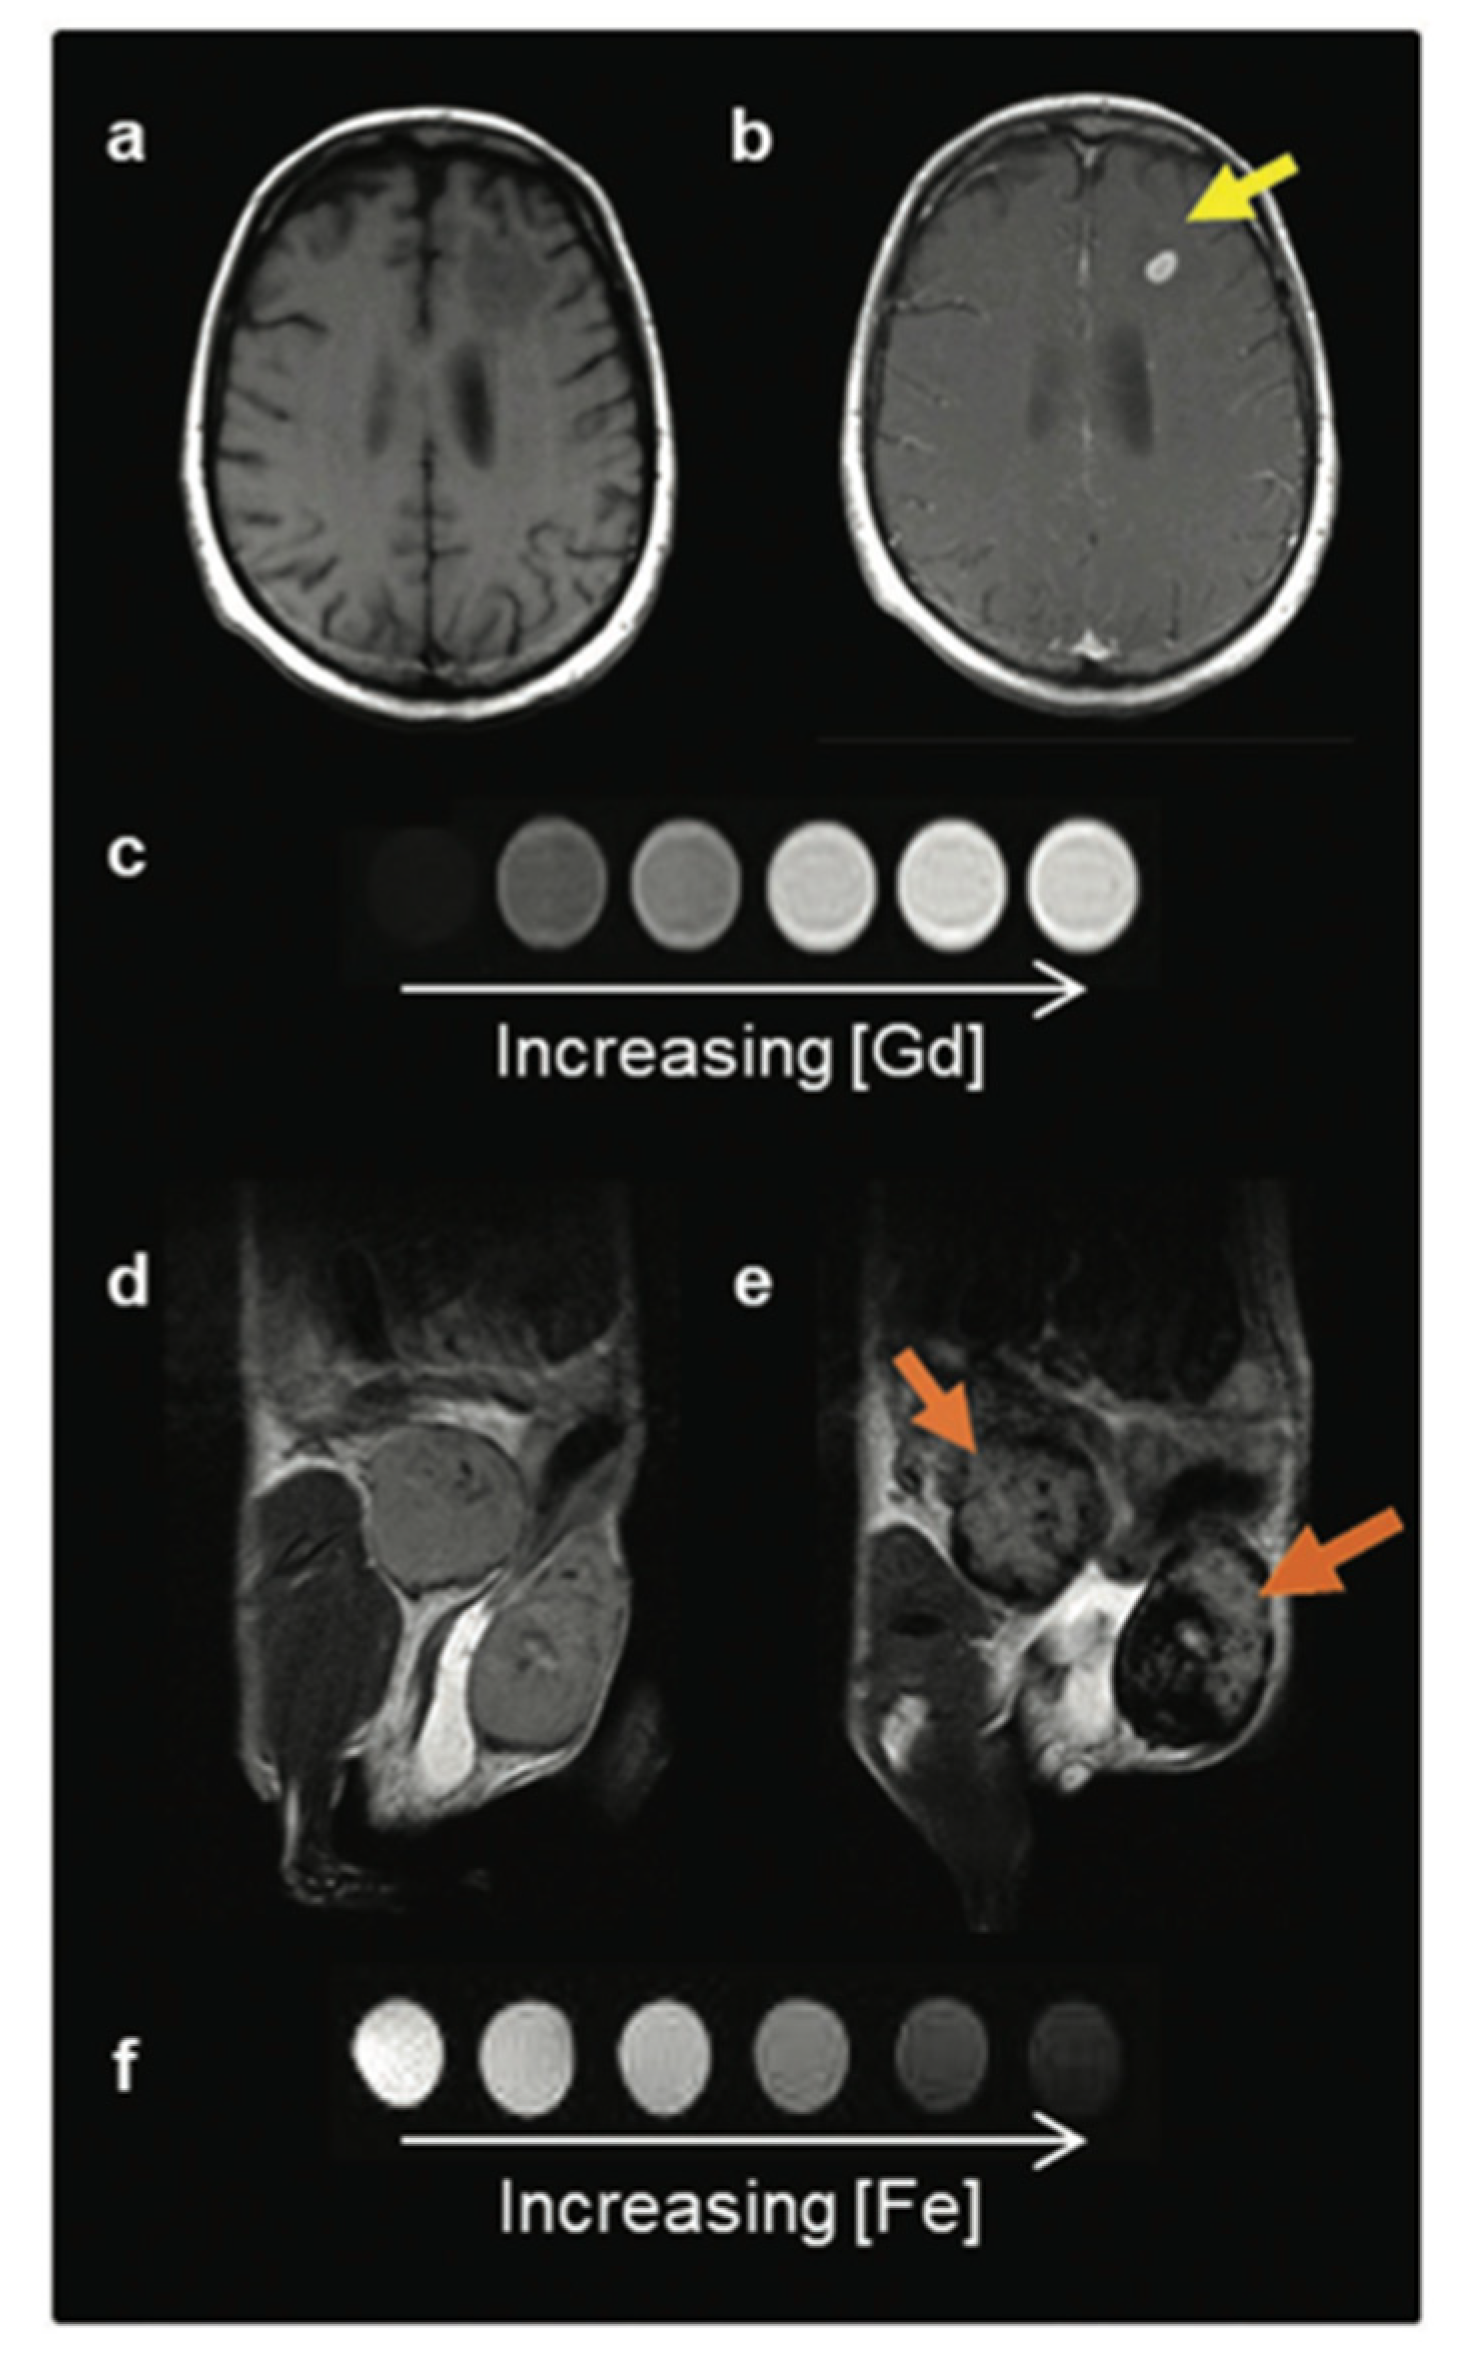

2.2. IONPs as MRI Contrast Agents

2.3. Contrast Agent Application in MRI